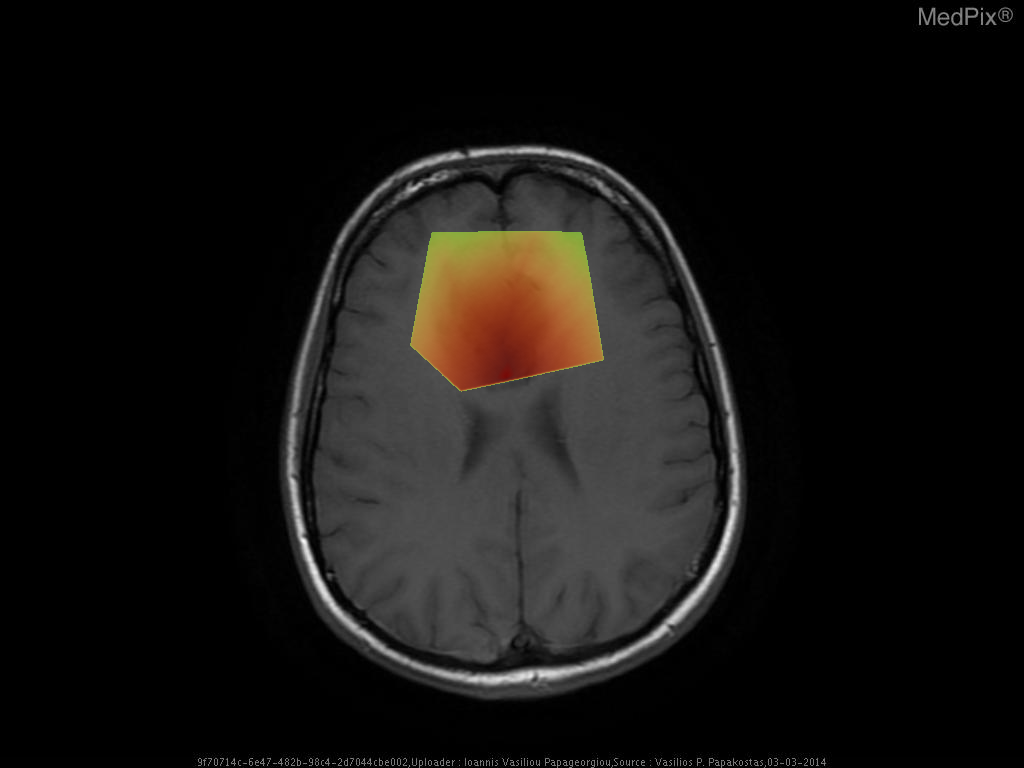

- Axial T1-weighted MRI brain shows a poorly defined, expansile lesion involving the image-right (patient-left) frontal lobe.

- The lesion demonstrates low T1 signal intensity relative to normal cortical gray matter.

- Minimal or no associated enhancement or hemorrhage visible on this non-contrast sequence.

- Mild mass effect evidenced by effacement of adjacent cortical sulci and mild displacement of the local midline toward image-left (patient-right).

- Gray-white differentiation appears blunted within the lesion region, suggesting infiltrative rather than circumscribed growth.

- No overt necrosis, cystic change, or intralesional hemorrhage visible on this slice.

- Surrounding brain parenchyma shows mild T1 hypointensity, potentially reflecting mild edema or infiltration.

- Ventricles appear slightly compressed on the image-right (patient-left) side, consistent with localized expansile mass effect.